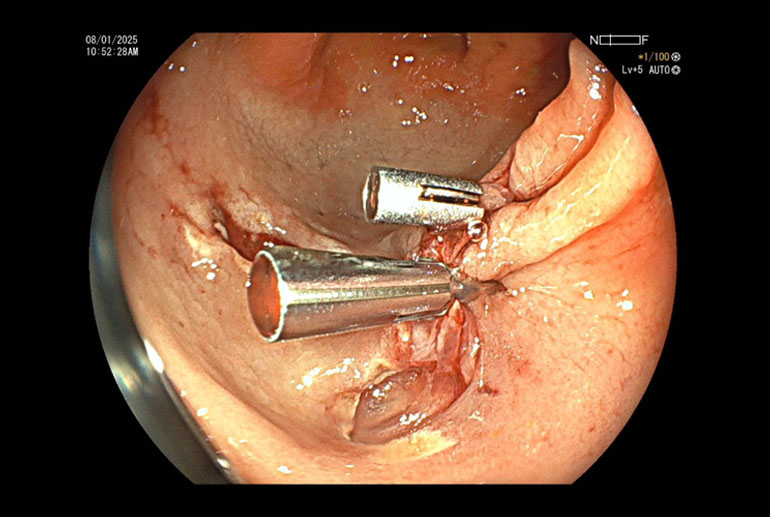

Case report: Underwater cold snare

Our patient had multiple polyps ranging between 7mm to 15 mm. Most of the polyps were flat, classified as Paris to AA. Several of these polyps were situated in cecum and ascending colon where colonic wall is quite thin and risk of perforation is higher. Using the technique of hydraulic immersion, it was possible to remove all these polyps with minimal risk to the patient. Post polypectomy site of the largest removed polyp was seen to be oozing blood; this was sealed with application of 3 hemoclips; effective hemostasis was achieved and patient did not suffer any complications.